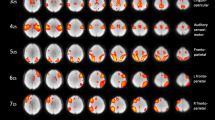

Comparative analyses between the pain and Control groups revealed that gray matter volumes in the left supplementary motor area (SMA), left primary motor area (M1), and left posterior cingulate cortex (PCC) were significantly greater in the Pain group than that in the Control group (Fig. 2 and Table 3). Comparative analyses also showed that gray matter volumes among these areas were all significantly greater in the BLP(+) subgroup than those in the Control group (Table 3 and Fig. S1).

Correlation analyses using the VBM data and NRS score revealed a significant correlation between NRS score and gray matter volume in the left M1, left PCC, and right superior parietal lobule (SPL) [Table 4, Fig. 3a and (Fig. 3b; R = 0.580, p = 1.93 × 10−5)].

a The regions showing the positive correlation between the NRS score and gray matter volume are superimposed on a normalized structural cerebral image. The color bar represents the t-score. Coordinates (X, Y, and Z values) are given in the Montreal Neurological Institute (MNI) space. b. Correlation analysis on the relative value of the gray matter volume at x = 15, y = 45, z = 60 (MNI coordinates) and NRS.